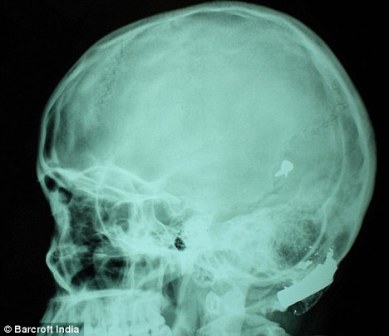

其中一顆子彈擊中她的左中耳,穿透了她的耳骨,然后擊中頭骨,嵌在了腦子里。另外兩顆子彈分別擊中她的右臂和心臟。印度Lok Nayak醫院的醫生稱,赫娜能夠康復完全是奇跡,她也足夠幸運。她的主治醫生稱:“當我們看到她的情況時,被嚇了一跳,幸運的是她活了下來。”

這顆子彈沒有損壞大腦中控制身體機能的部分。盡管赫娜的手術很成功,但醫生表示,她還有出現感染和并發癥的可能。子彈毀掉了她的中耳,可能導致她耳聾。(楊柳)